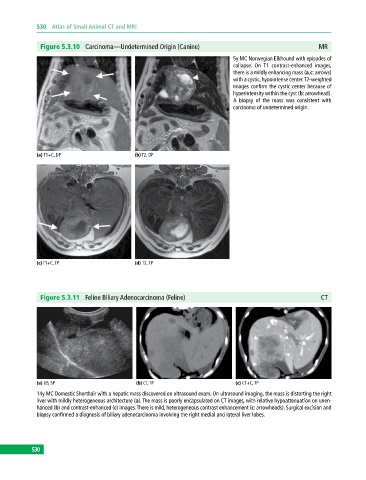

Figure 5.3.10 Carcinoma—Undetermined Origin (Canine) MR

5y MC Norwegian Elkhound with episodes of

collapse. On T1 contrast‐enhanced images,

there is a mildly enhancing mass (a,c: arrows)

with a cystic, hypointense center. T2‐weighted

images confirm the cystic center because of

hyperintensity within the cyst (b: arrowhead).

A biopsy of the mass was consistent with

carcinoma of undetermined origin.

(a) T1+C, DP (b) T2, DP

(c) T1+C, TP (d) T2, TP

Figure 5.3.11 Feline Biliary Adenocarcinoma (Feline) CT

(a) US, SP (b) CT, TP (c) CT+C, TP

14y MC Domestic Shorthair with a hepatic mass discovered on ultrasound exam. On ultrasound imaging, the mass is distorting the right

liver with mildly heterogeneous architecture (a). The mass is poorly encapsulated on CT images, with relative hypoattenuation on unen-

hanced (b) and contrast‐enhanced (c) images. There is mild, heterogeneous contrast enhancement (c: arrowheads). Surgical excision and

biopsy confirmed a diagnosis of biliary adenocarcinoma involving the right medial and lateral liver lobes.